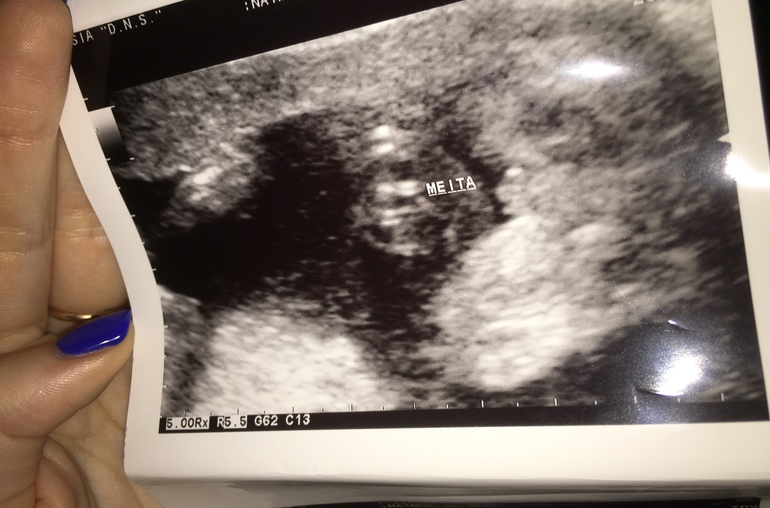

Девочка или мальчик? (фото)

ЗаморочкиЗдравствуйту. На узи была в 19-20 недель, сказали, что девочка.... Показали фото свекрови, и она твердит, что мальчик ( тоже доктор но по другой специальности), завела меня только в заблуждение..... А что видите вы?

Ничего я не увидела на Вашем фото, даже малыша не разобрать. Мне пол в 12 нед сказали, в 3д перевел узист и все видно.

На последнем ничего не поняла. По первому точно девчачье. Мне такое со всеми тремя показывали )))))